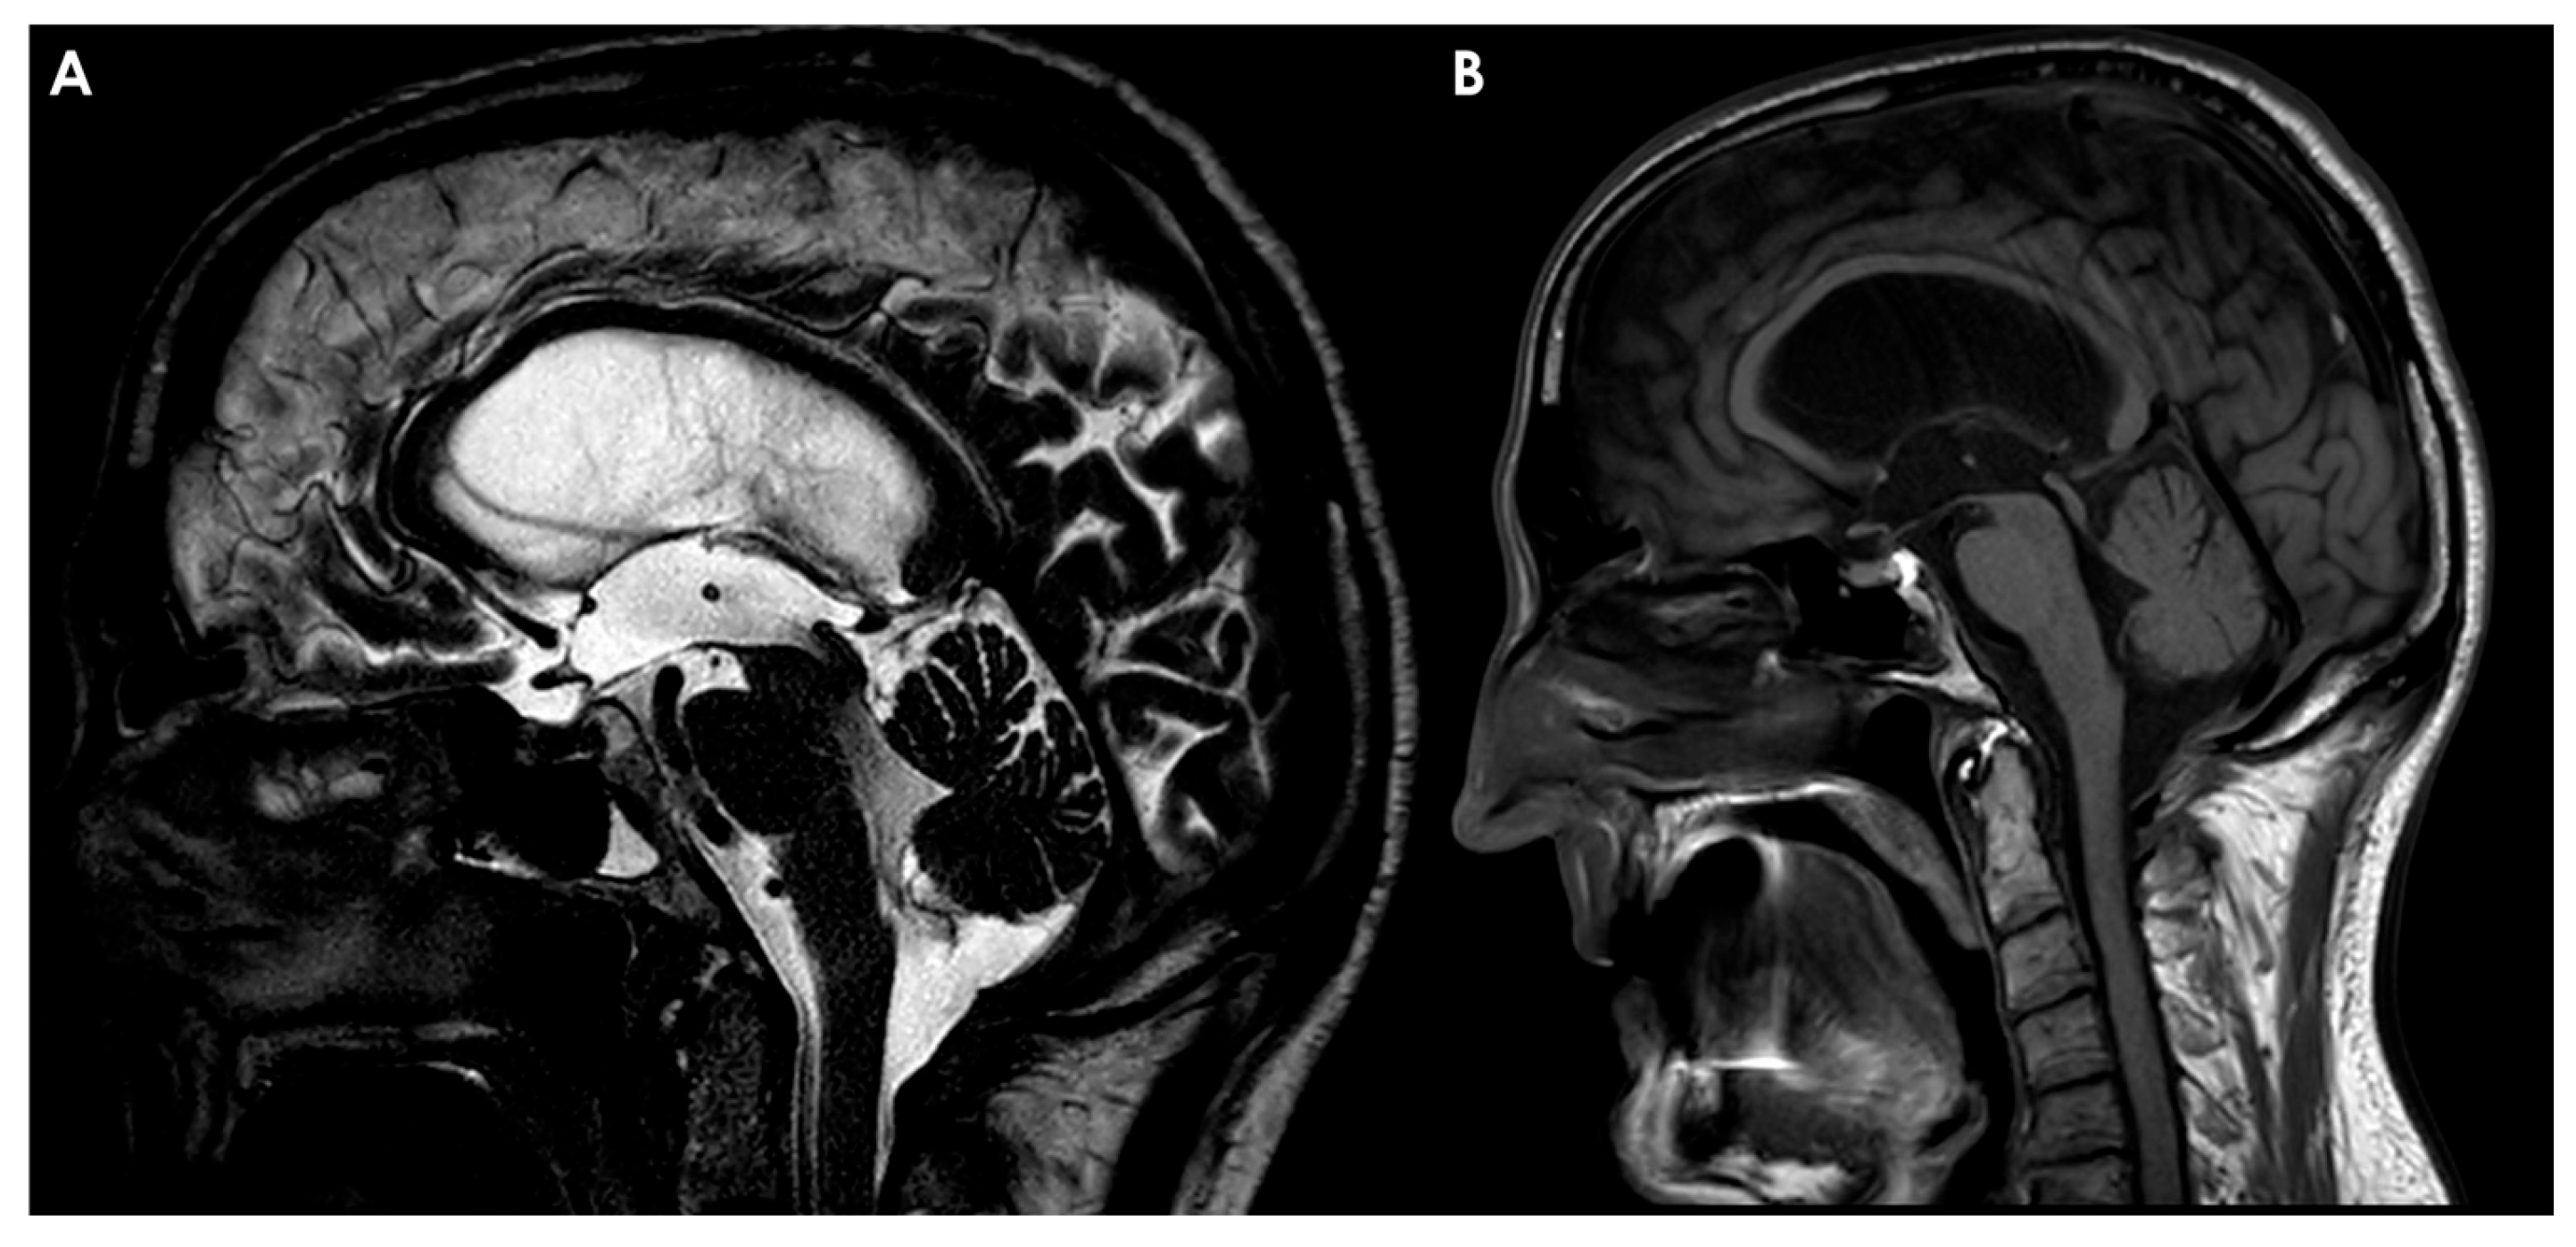

4.1.1. Hydrocephalus

4.1.2. Endoscopic Third Ventriculostomy

- -

- Inserting an endoscope through the brain parenchyma, usually via the right frontal lobe.

- Navigating the endoscope through the foramen of Monro into the third ventricle.

- Creating a stoma at the floor of the third ventricle, allowing CSF to flow directly into the interpeduncular cistern [134].

4.2. Subarachnoid Hemorrhage